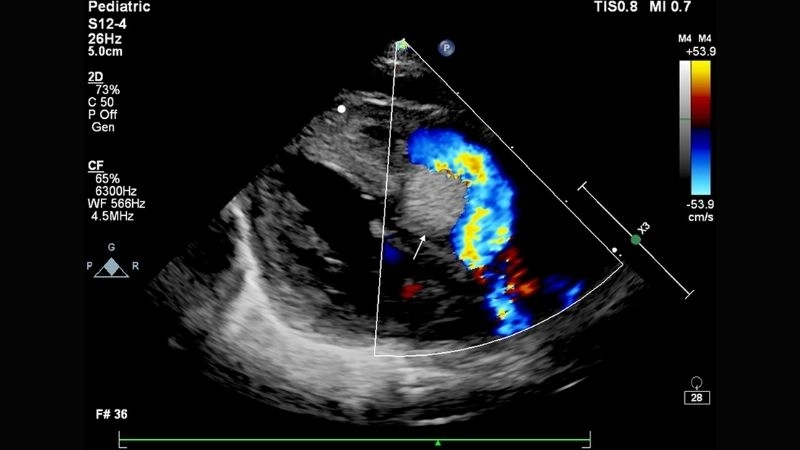

Rhabdomyoma is a rare benign tumor of striated muscle, commonly affecting the heart in children. Images often highlight cardiac masses that disrupt heart rhythm and function.

Detailed look at cardiac rhabdomyoma condition